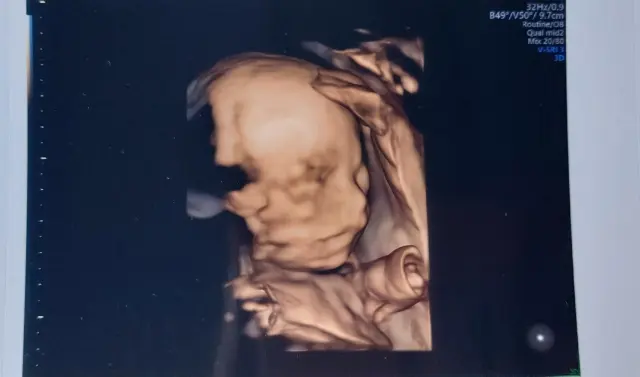

Fotogalerie